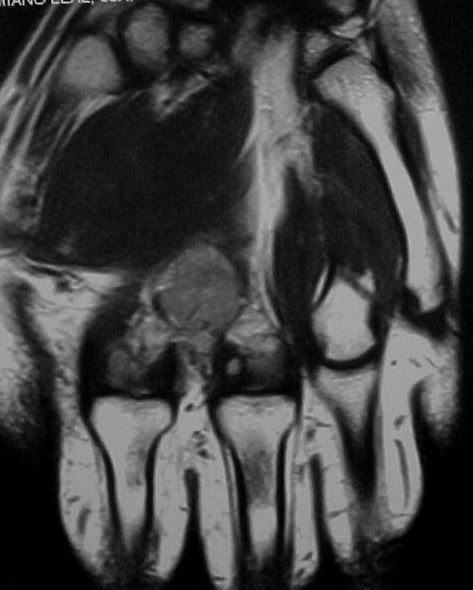

36y, male, Discrete pain and increase of volume between the 2nd and 3rd MCs

Case to follow the sent by Kyung, showing a glomus tumor in an unusual place

Glomus tumors